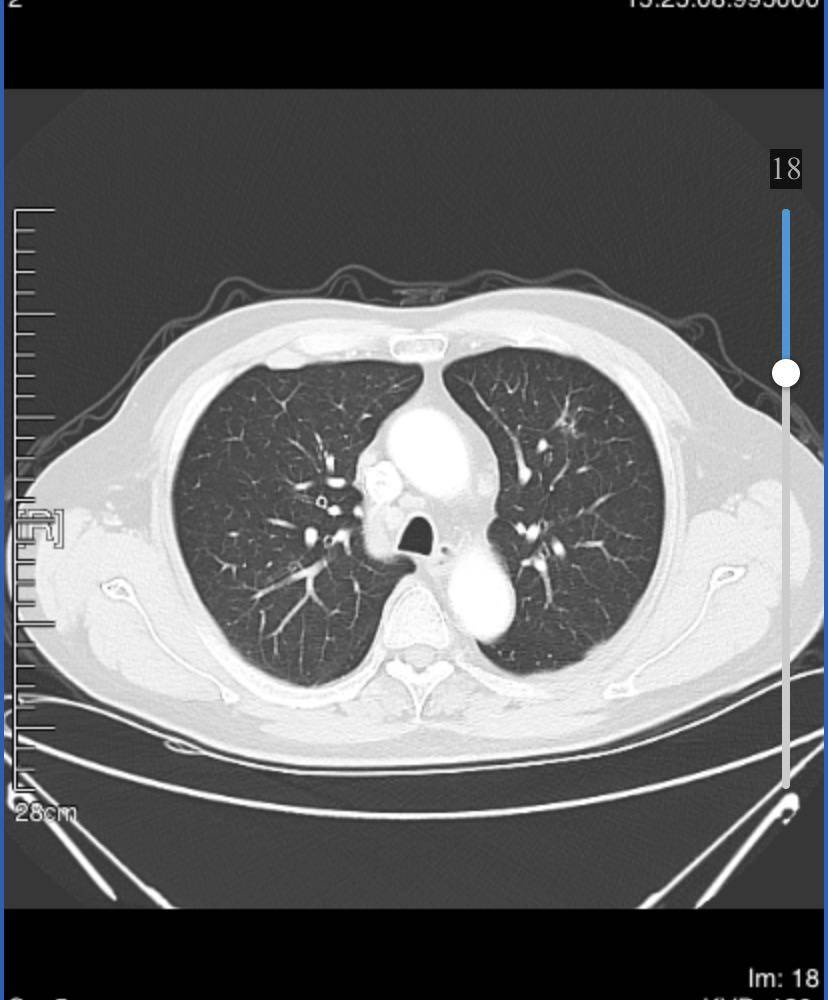

8月21日胸ct显示右肺下叶占位,3.4cm*3.0cm,纵隔及右肺门多发增大淋巴结;右前肋胸膜外脂肪间隙内淋巴结肿大;左肺上叶磨玻璃结节1.6cm,微浸润性腺ca。

目前已经服药1个月,10月23号拍ct,右下肿瘤2.4*2.5,淋巴结略有缩小,磨玻璃结节1.4…